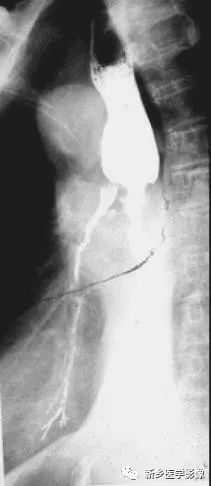

中段食管癌并發(fā)食管氣管瘺鋇餐造影圖像

吞鋇后食管中段狹窄,并見(jiàn)支氣管顯影